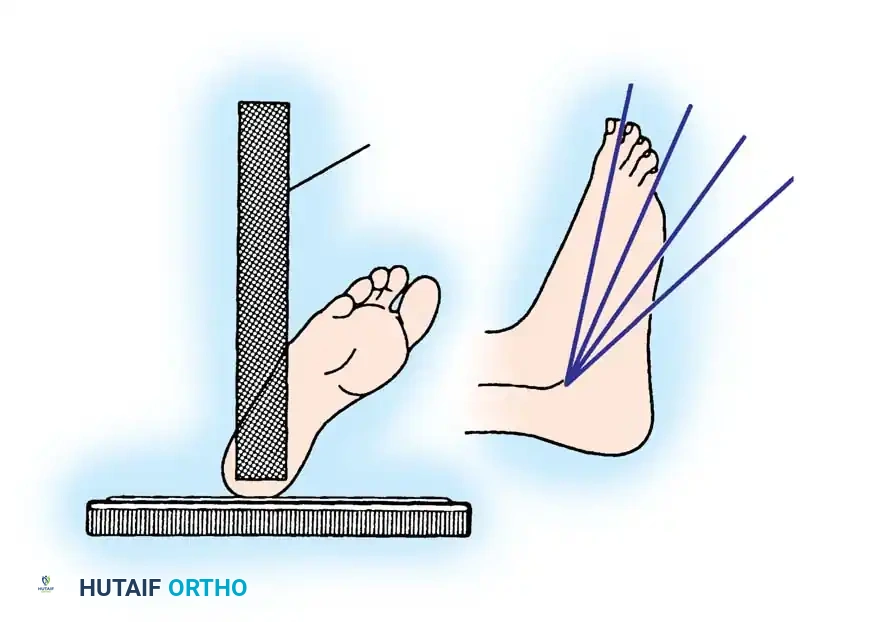

The Brodén View

The Brodén view is critical for visualizing the posterior facet. It is obtained by internally rotating the leg 40 degrees with the ankle in neutral dorsiflexion. The x-ray beam is then angled cephalad at 10, 20, 30, and 40 degrees to visualize different portions of the facet from posterior to anterior.

While plain films are essential, CT scanning is the gold standard for evaluating intraarticular calcaneal fractures. Scans must be ordered in two specific planes:

* Semicoronal Plane: Oriented perpendicular to the normal position of the posterior facet. This is the most critical view for assessing articular comminution and classifying the fracture.

* Axial Plane: Oriented parallel to the sole of the foot, excellent for evaluating the calcaneocuboid joint and the sustentaculum tali.